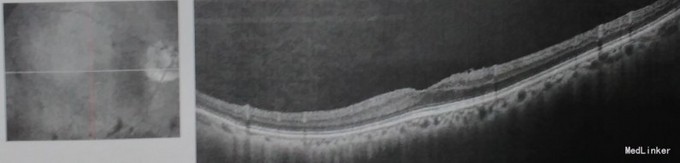

查体: VOD 0.9,VOS:0.8,双眼中央前房4CT,周边1/2CT,虹膜纹理清,瞳孔3×3mm,晶体混浊++。眼底 C/D约0.8。双眼房角开。 辅查: 右眼视盘视神经纤维层下方厚度变薄